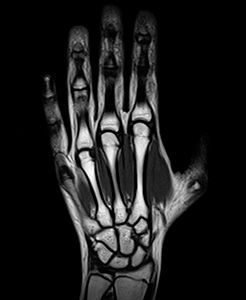

МРТ кисти руки и лучезапястного сустава

МРТ кисти руки является экспертным диагностическим исследованием, направленным на оценку состояния мягких и костно-суставных тканей, а также на выявление любых имеющихся патологий. МРТ кисти позволяет провести высокоинформативное исследование и выявить даже незначительные патологические процессы в костях, сухожилиях и связках на ранних стадиях их развития. Сустав кисти является самым сложным по своему анатомическому строению, способным выполнять целый ряд функций. В то же время это один из самых уязвимых для разного рода заболеваний и травм. МРТ кисти и лучезапястного сустава позволит определить причину болевых ощущений и ограниченности движений, которые может испытывать пациент. С высокой точностью она позволит поставить диагноз и назначить эффективное лечение. При необходимости получения максимально чёткого изображения, МРТ суставов кисти проводится с применением контрастного вещества.